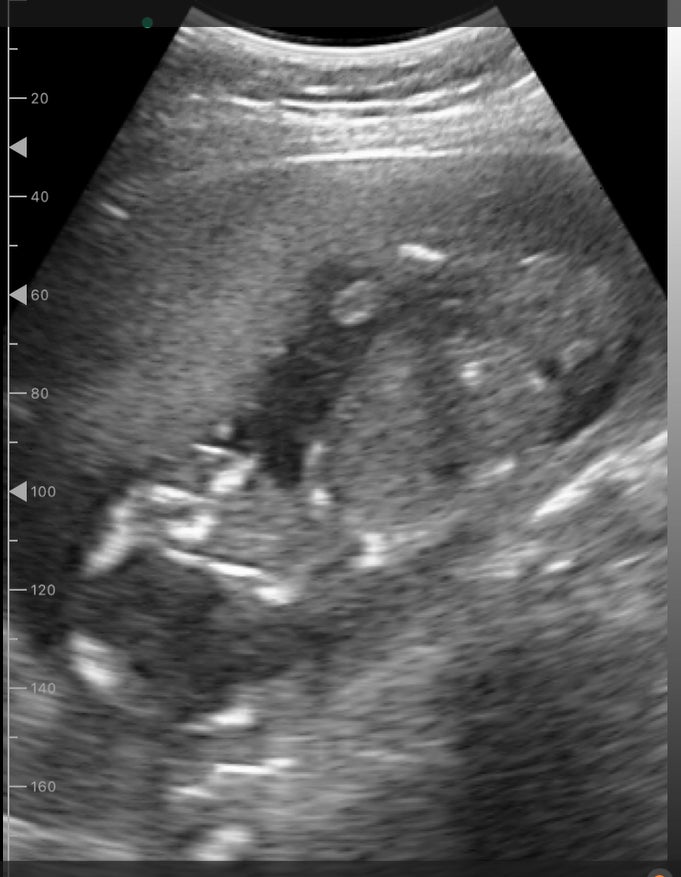

「ポケマム2」は、妊婦さんが自宅でスマートフォンやタブレットを使って、お腹の赤ちゃんのエコー画像を確認できる家庭用エコーシステムです。月額9,980円でご利用いただけ、初回申込み時には専用ジェルおよび往復送料を含む初回キット料金4,000円が加算されます。